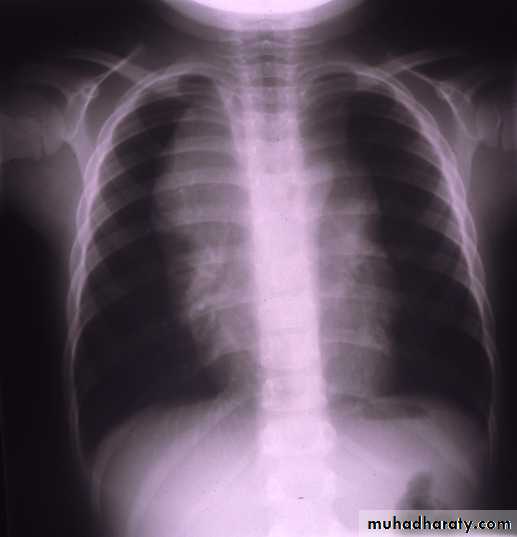

Before Rx.After Rx.